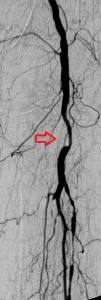

In this patient, a 67 year-old woman with long-standing diabetes, there was a plantar ulcer of her anterior left forefoot that resisted healing despite many noninvasive treatments. Her podiatrist referred her to me and her sonographic and angiographic investigations revealed multiple significant stenoses in her distal left superficial femoral artery (LSFA), left popliteal artery, and her anterior tibial artery. Her posterior tibial artery was occluded and her chief path of blood flow to the left foot was her left peroneal artery. Her arterial paths above the distal left SFA were open and she had stage 3 chronic renal insufficiency. Faced with the dilemma of continuing foot infection and potential limb loss and worsening renal insufficiency following exposure to radiocontrast, she put off endovascular revascularization of the arterial narrowings for sometime, finally caving to pressures from her son.

After instituting strategies to minimize contrast-induced nephropathy, I employed atherectomy of the distal LSFA and popliteal stenoses and angioplasty of the multifocal stenoses of her anterior tibial artery down to the dorsalis pedis artery to restore reasonable flow to her foot that helped the ulcer heal.

Images in the top panel illustrate her disease before the interventions, those in the middle panel illustrate some intraprocedural steps (balloon angioplasty), while those in the bottom panel illustrate improved blood flow to the foot following treatment.